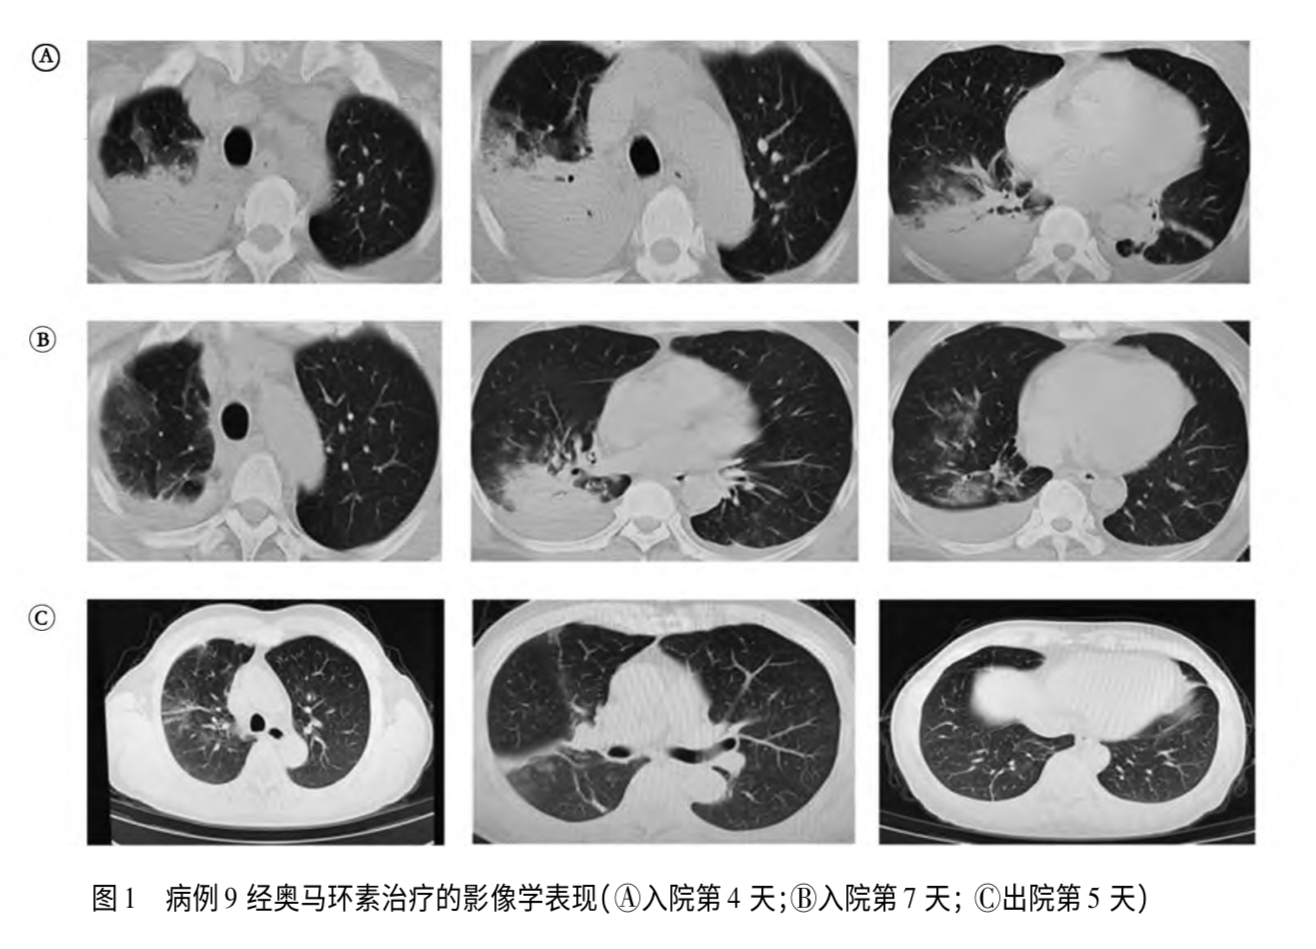

北京航空总医院曾收治两名鹦鹉热患者,图为其接触发病史及影像学检查。 图/相关论文

南京医科大学附属南京医院收治的一名鹦鹉热患者影像资料。图/《15例鹦鹉热衣原体肺炎诊疗分析》